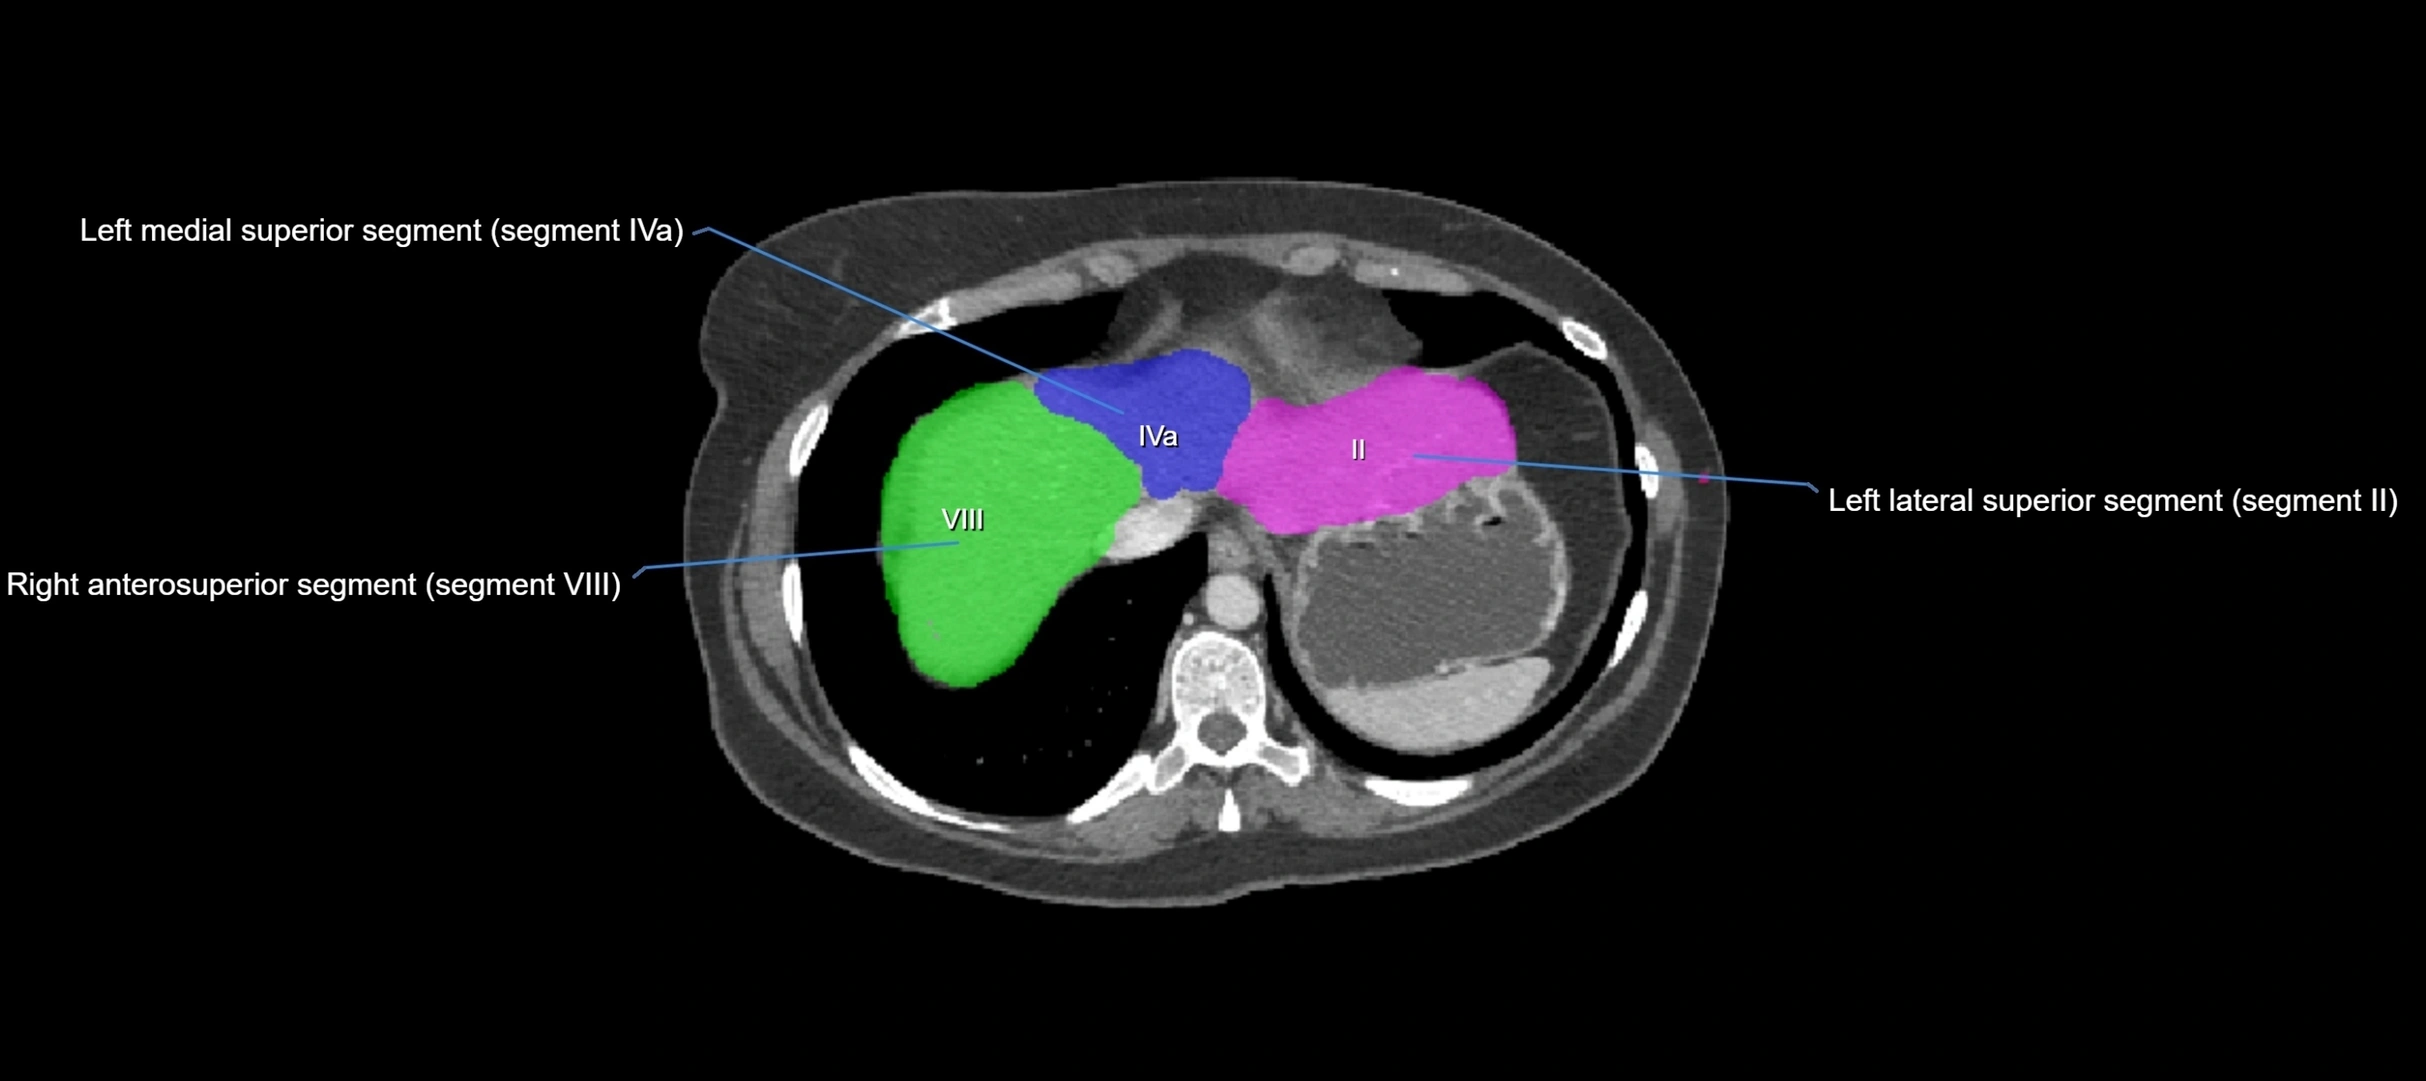

The caudate lobe of the liver is a distinct anatomical subdivision of the liver, designated as segment I in Couinaud’s classification. It lies on the posterior surface of the liver, between the fissure for the ligamentum venosum (left boundary) and the groove for the inferior vena cava (IVC) (right boundary). Superiorly, it is related to the posterior liver surface, and inferiorly it is separated from the left lobe by the porta hepatis.

CT Appearance

CT Pre-Contrast:

• Caudate lobe appears as a soft-tissue density, isodense to the rest of the liver

• Enlargement may be appreciated in cirrhosis or Budd–Chiari syndrome

CT Post-Contrast:

• Homogeneous enhancement in the portal venous phase, similar to rest of liver

• Independent venous drainage into the IVC may be visualized

• Lesions follow characteristic CT enhancement patterns (HCC: arterial hyperenhancement with washout; hemangiomas: peripheral nodular enhancement with centripetal fill-in)

CT Venous Phase (functional significance):

• Caudate lobe often enhances relatively more than other lobes in Budd–Chiari syndrome, due to preserved venous outflow

CT Image